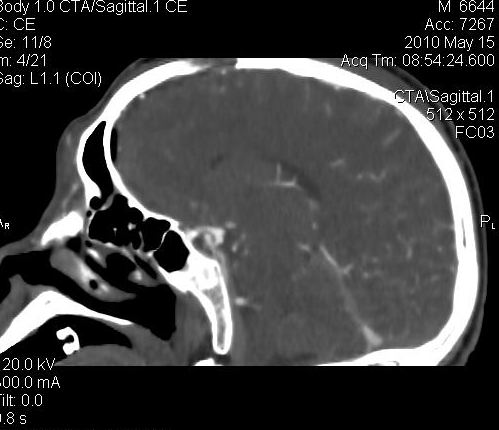

男.60岁,渐进性意识不清,ct检查双侧额颞顶部硬膜下血肿,开颅术后行脑血管cta,大脑中动脉起始部见一瘤状血管扩张。请各位老师留下宝贵意见

图片质量较差,是机器?